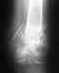

Re: Перелом лодыжки с осложнением

Оперирующий врач, посмотрев снимок месячной давности рекомендовал походить в гипсе еще 3 недели (уже ходя с нагрузкой в гипсе) снять гипс, сделать снимок и с чистой ногой, пешком прийти к нему. А мне неудобно ходить в гипсе - могу только наступать (держать равновесие без костылей). Вся проблема в том что больница в 100 км от моего поселка и нет возможности часто видеть врача. Вот я и прошу консультации в интернете.